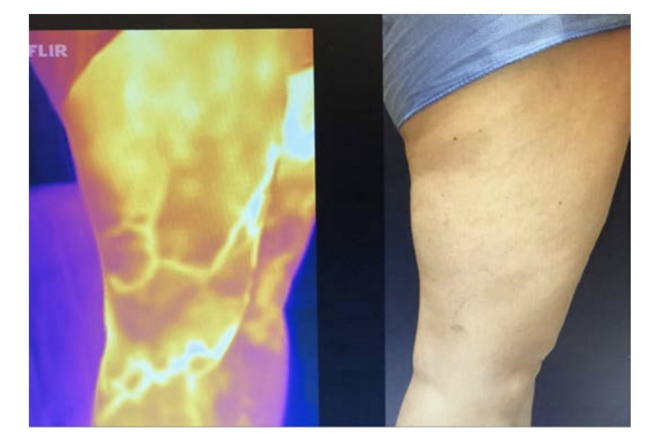

Over the decade 2010-2020, thermal imaging cameras have become more available, cheaper, smaller and more usable. In 2015 the authors started investigating the use of TI for superficial vein disease. It soon became obvious that varicose veins showed up very well on thermal imaging. Some authors have concluded that the increased heat over veins is caused by inflammation.4 We believe that we may be the first to describe that the increased heat pattern seen over the insufficient superficial veins is due instead to the core blood leaking toward the skin surface and not from inflammation. Venous blood in the deep veins has previously supplied the muscles and other structures deep to the deep fascia and is close to core body temperature (approximately 37°C). Conversely, venous blood in the normal superficial veins of the leg is blood that has been through the capillary network of the skin and subcutaneous tissue and so has equilibrated with skin temperature which is typically around 29-30°C.6 On thermal imaging normal (competent) superficial veins therefore do not show up as thermographically different from the skin and are therefore not detected. In superficial venous disease blood refluxes from the deep veins into the superficial veins and down the leg through incompetent valves, most commonly the great saphenous vein (GSV), the refluxing blood is substantially hotter than the skin and heat conducts to the surface and is detected as an area of elevated skin temperature that overlies the course of the incompetent superficial vein and is easily seen on TI (Figure 2 and 3 A&B). It has been suggested that the temperature differences are caused by inflammation of the vein, despite the fact that for simple varicose veins there are none of the markers of inflammation, redness and swelling of surrounding tissue, both of which are clearly seen in superficial thrombophebitis. Histological studies of simple varicose veins confirm this with the main finding being intimal hypertrophy and fibrosis with muscle thinning.9,10 In addition, if an individual is imaged while standing the vein pattern is very clear, 2-3 minutes after lying down the pattern is no longer present, if they stand again the vein pattern reappears. The authors believe this is clear evidence of the transient nature of the signal and its association with reflux. If it were caused by inflammation the pattern would be sustained for an extended period. The incompetent trunk vein is not usually seen as it lies deeper in its own fascial sheath. Adjacent structures to the incompetent truck vein are also at core body temperature and equally conduct heat to the surface so no excess heat is detected. Once the vein escapes the deep fascia and comes closer to the skin, the surface temperature is elevated and is typically around 33°C. This consistently creates a localised elevation in temperature along the incompetent vein of approximately 3°C when compared to nearly all adjacent anatomy, which is easily detected with modern TI cameras with sensitivity of 0.1°C.

It might be imagined that obese legs would not display vein patterns in the same way as slim individuals as the insulating effect of the thicker subcutaneous tissue was greater.4 In practice this does not seem to be the case, as the skin surface in the obese or edematous patient is likely to be cooler than that of a slim person, thus the relative temperature difference is maintained. While there has been no study of this reported in the literature the authors have not found thermal imaging of the obese leg to be any less useful (Figure 2 and 3).

To see if there was a change in diagnostic results following the introduction of thermal imaging, two consecutive patient series were compared. The first series was before the introduction for TI, and the second after TI was routinely and consistently used on all patients prior to DUS. Then the frequencies with which the major trunk vein segments were identified as incompetent were compared between the two-patient series. For all segments there were numerical increases after TI introduction and comparing all identified segments there was a 24.6% increase in trunk vein incompetence which was statistically significant. For the GSV while there was a modest increase in detection, that was not statistically significant. This was to be expected as TI is not usually capable of detecting the incompetent trunk vein in the thigh, but highly capable of detecting the GSV below the knee. The detection of incompetence from the AAGSV and the PAGSV were both increased by 2- and 3-fold, respectively but as the overall frequencies are low these failed to reach statistical significance in this relatively small series of patients. The trend toward increased detection of incompetent AAGSV and PAGSV was not a surprise to the investigators as they tend to run closer to the surface than the truncal GSV. TI can detect lateral and upper posterior thigh vein incompetence which guides the sonographer to look in areas that might otherwise be less obvious and is often missed on routine exam. Additionally, it has served as a very beneficial tool for patient education, allowing visual discussion of venous status that is much more visually comprehensible to the patient than traditional DUS data (Figure 3).